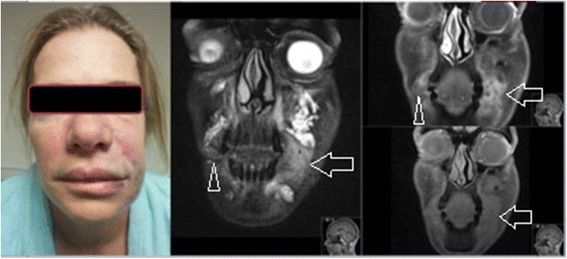

Ironically, filler isn’t what distorts the face. Poorly placed filler, lack of restraint, and repeated treatments can and will create this problem over time.

Aside from the much more serious risks that come along with any medical procedure, dermal fillers can cause some more common side effects like migration, hardening, and potentially worsen facial sagging (though that’s heavily debated).

There’s also the fun fact that filler doesn’t necessarily always break down on its own…

…it can remain in the body for as long as five years, with at least one case of detection after 10.

When filler is injected, there’s a healing response along that pathway. Each injection introduces minor internal scarring, and with frequent visits, that scar tissue can accumulate.

This can interfere with lymphatic drainage (aka causing fluid retention) and overall contribute to the overly-smoothed, puffy, “pillow face” effect that people instinctively react to.